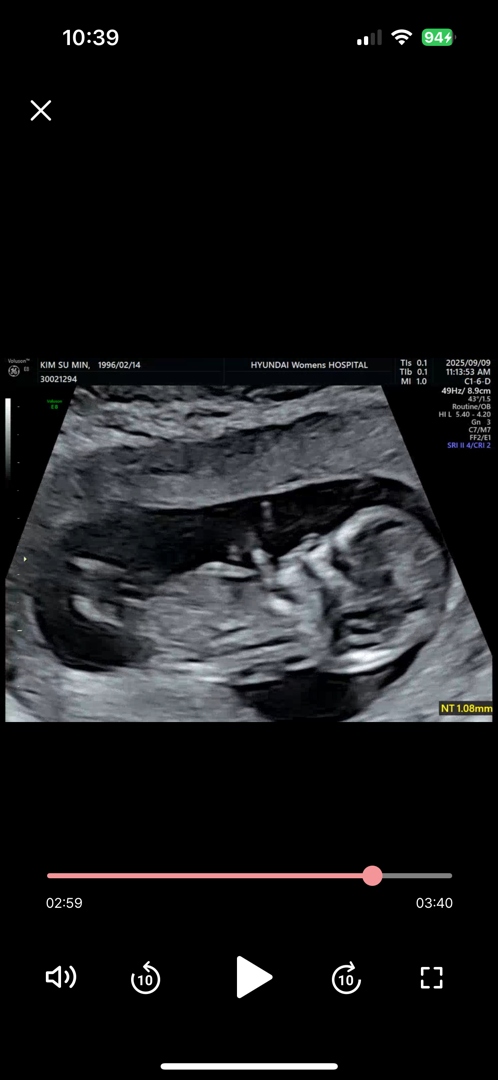

12주 각도법 고수님들 봐주세용 ~!

저는 아무리 봐도 잘 모르겠네요 하하 ㅠㅠ